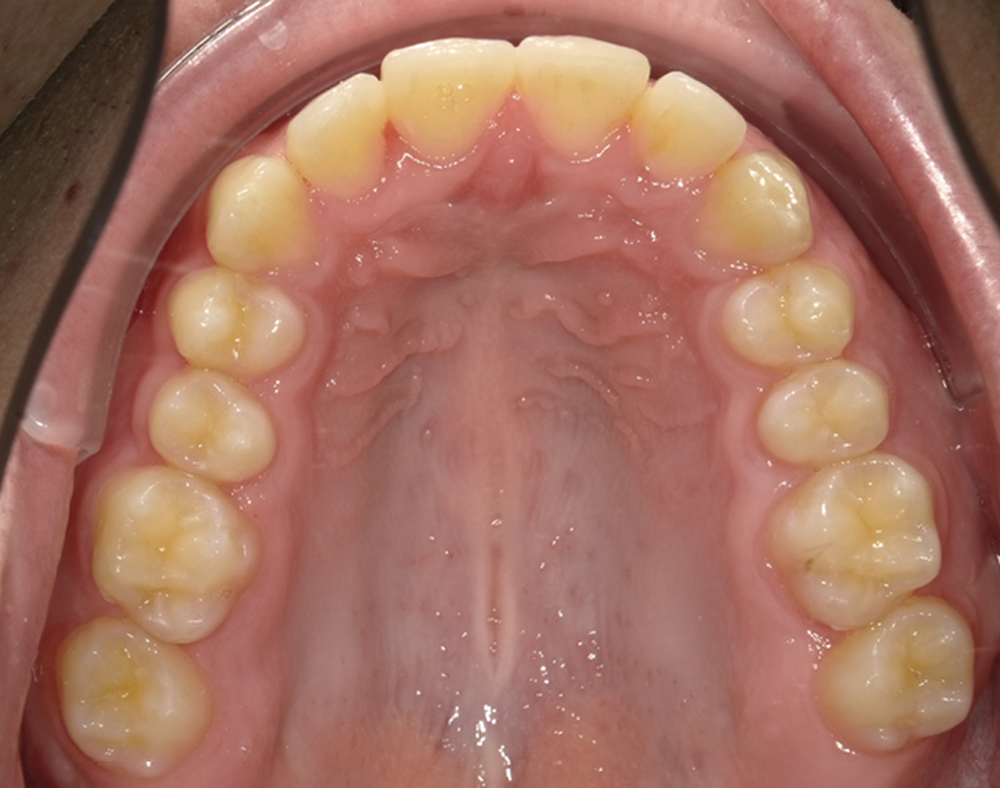

C’est à ces questions que nous permettront de répondre les deux premiers conférenciers, parodontologistes : le Dr Béatrice Straub nous présentera le renfort parodontal minéralisé, technique qu’elle a développée et pratique depuis de nombreuses années, pour éviter les préjudices des mouvements orthodontiques à risque, notamment lors des décompensations préchirurgicales (fig. 1a-d) ; le Pr Anton Sculean abordera le thème des greffes, avec leurs indications, les différentes techniques à privilégier et illustrera ses propos par de nombreux cas cliniques aux résultats esthétiques impressionnants.